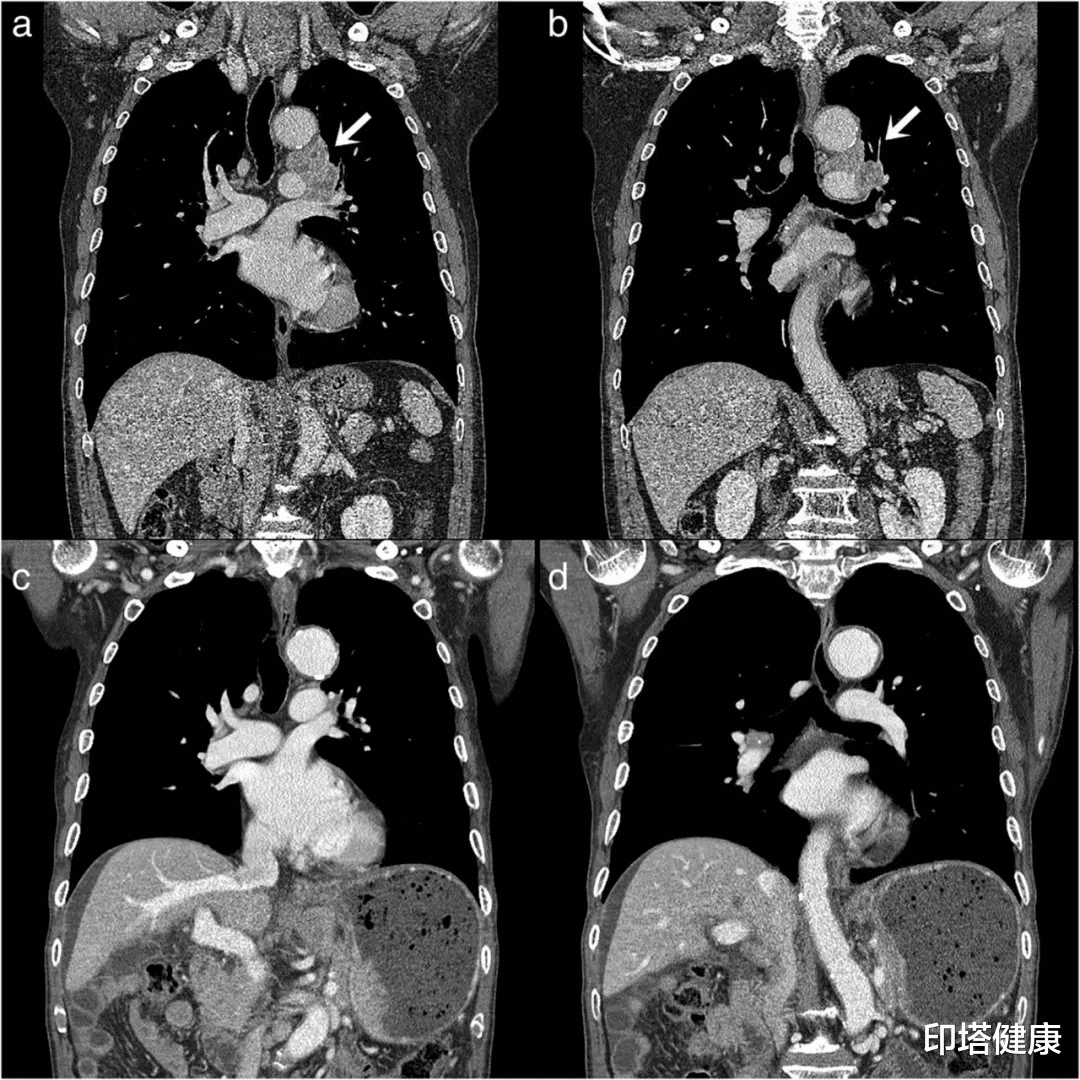

图注:(a和b)胸部CT示左上叶肿瘤 , 左肺门及纵隔淋巴结肿大 。 (c和d)胸部CT显示既往肿瘤病变完全消失 。

52个月后 , 由于患者无法进食、身体严重衰弱 , 再次入院就诊 。 胸部X光片显示没有左肺门肿大的病灶 。 胸部CT扫描证实之前的SCLC在左上叶、纵隔和肺门中的病灶完全缓解 。